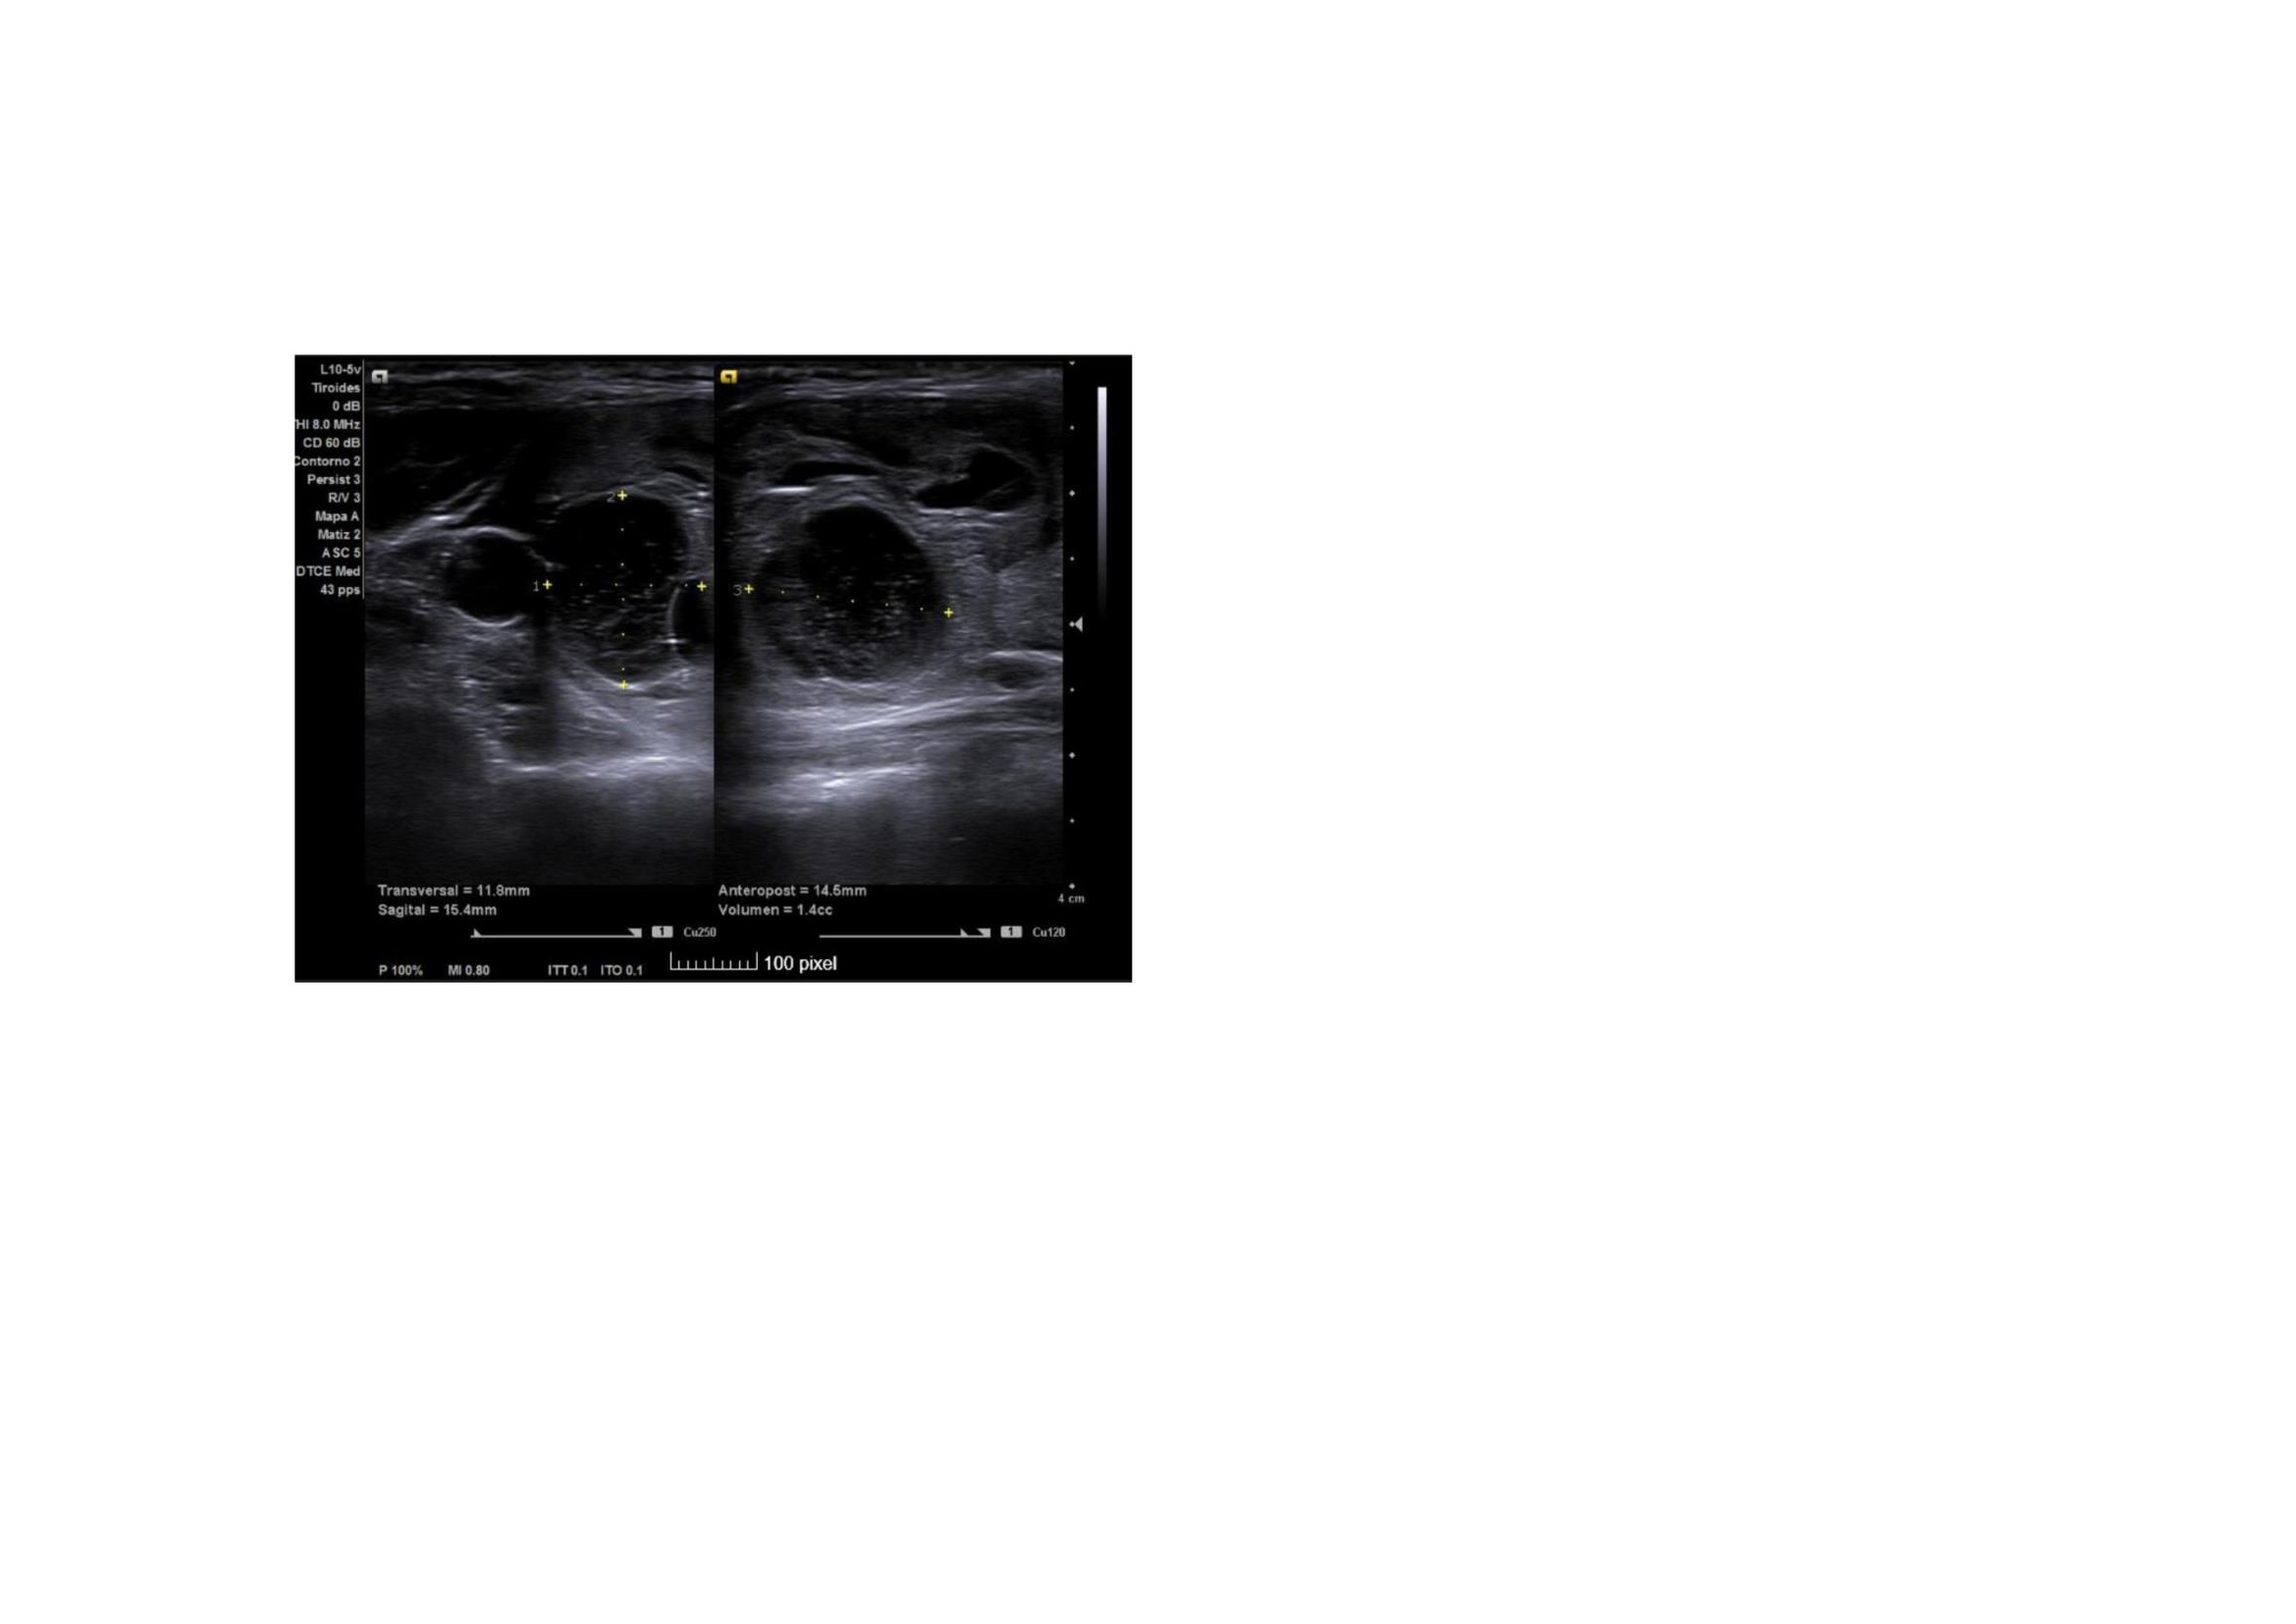

Ecografía clínica: En lóbulo tiroideo derecho observamos nódulo mixto sólido-quístico, de 11,8 x 14,5 x 15,4 mm, de bordes bien delimitados mayoritariamente hipoecogénico, parcialmente tabicado a nivel inferomedial, más alto que ancho con micro calcificaciones en su interior. TIRADS 5.

Ecografía Hospital: Lóbulo tiroideo derecho aumentado de tamaño (2,2 cm de diámetro anteroposteior), por la presencia de un nódulo sólido, heterogéneo, levemente hipoecoico, bien definido, con áreas de degeneración quística y calcificaciones groseras en su interior, de 22 x 21 x 33 mm. Resto del tiroides sin alteraciones. No se aprecian adenopatías cervicales. Glándulas salivares sin alteraciones. Conclusión: Nódulo en lóbulo tiroideo derecho, único, TIRADS 4.